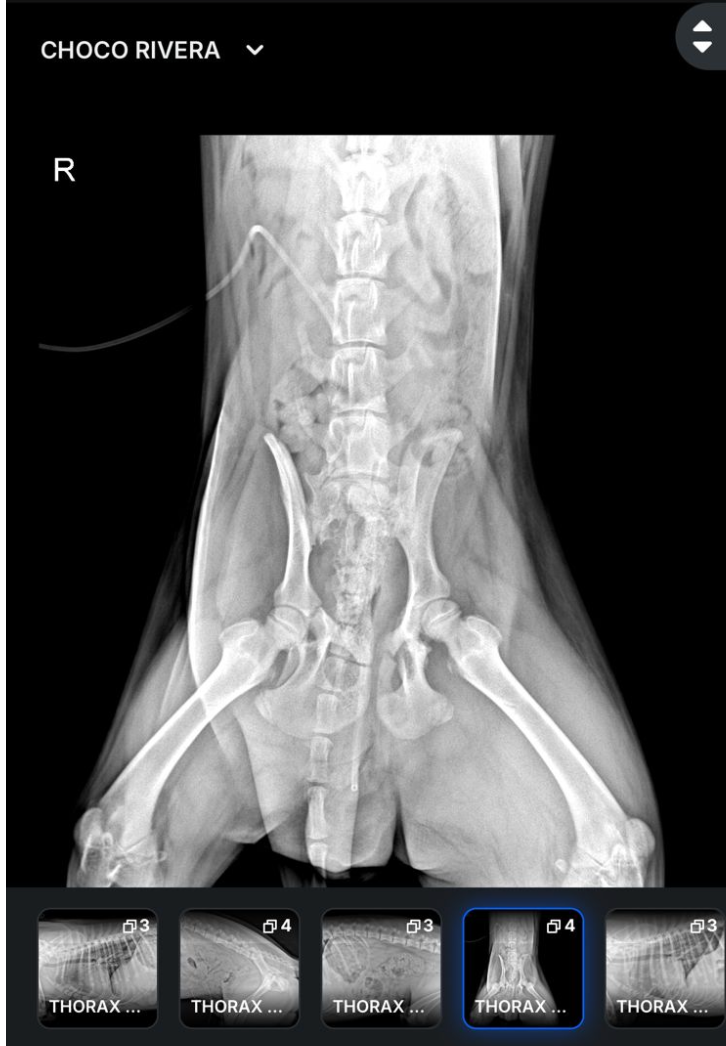

Choco suffered multiple fractures to his leg and hips and required immediate veterinary care. To ensure he received treatment without delay, I covered the upfront emergency costs.

Choco sufrió múltiples fracturas en la pierna y en la cadera, por lo que necesitó atención veterinaria inmediata. Para que pudiera recibir el tratamiento necesario sin ningún retraso, yo cubrí los gastos médicos de emergencia de forma inmediata.